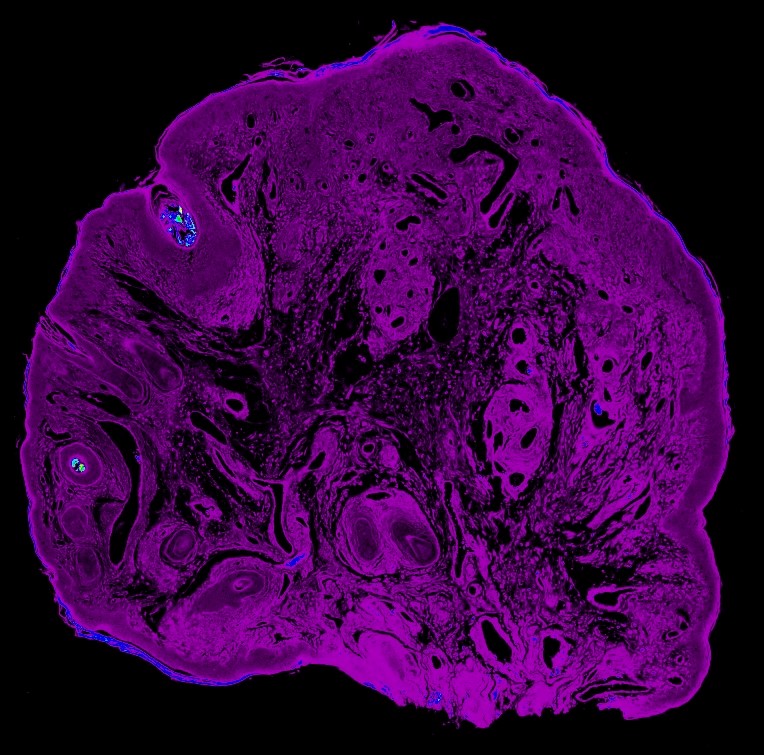

Lunar bajo la lupa